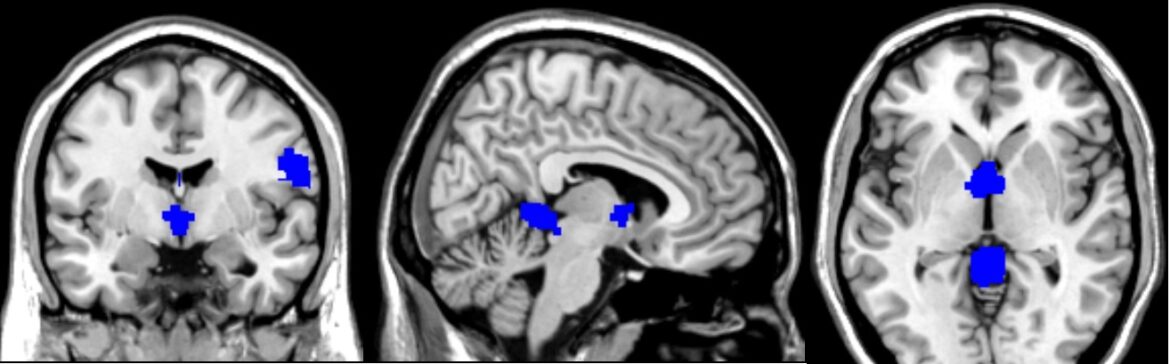

Recent research has brought significant insights into the neurobiological underpinnings of FND by using a technique called voxel-based morphometry (VBM). This method allows scientists to detect subtle differences in brain structure, particularly in grey matter volume, across groups of patients compared to healthy controls. By aggregating data across multiple studies, researchers have conducted a comprehensive voxel-wise meta-analysis that sheds light on where and how the brains of individuals with FND may structurally differ from those without the disorder.

Key Findings: Where the Brain Changes

By analyzing data from studies involving more than 150 patients with FND and nearly 240 healthy controls, researchers were able to map consistent patterns of grey matter changes in the brain. These patterns varied depending on the subtype of FND but showed significant overlap in certain brain regions.

Increases in Grey Matter Volume

Some brain areas showed an increase in grey matter volume in individuals with FND, suggesting possible adaptive changes, heightened activity, or even compensatory mechanisms:

- Cerebellar Vermis (Lobules IV and V): These midline cerebellar structures are known for coordinating motor functions and processing emotional responses. Increases here were particularly prominent in patients with movement disorders.

- Right Postcentral Gyrus: This region corresponds to the primary somatosensory cortex, responsible for processing tactile information. Changes here may reflect heightened attention to bodily sensations or altered sensory processing.

- Left Supplementary Motor Area (SMA): Involved in planning and initiating movement, as well as integrating sensory and emotional cues. This area was consistently found to have increased grey matter in patients with sensory symptoms.

- Thalamus: A central hub for sensory and pain signals, the thalamus also showed increased volume, especially in patients experiencing chronic pain.

Decreases in Grey Matter Volume

Other regions exhibited reductions in grey matter, which might signify loss of function, maladaptive neuroplasticity, or stress-related atrophy:

- Right Inferior Longitudinal Fasciculus: A white matter tract involved in connecting visual processing areas with the limbic system, important for integrating emotional and sensory experiences.

- Left Insula: A critical area for emotional awareness, interoception (the sense of the internal state of the body), and pain perception. Reduction in volume here was observed in patients with sensory symptoms.

- Cingulate Cortex: Specifically, the median cingulate/paracingulate gyri showed decreased volume in patients with functional movement disorders. These areas are involved in emotion, attention, and conflict monitoring.

Interestingly, the structural changes did not consistently correlate with symptom severity or disease duration. This finding suggests that these alterations might be present regardless of how long someone has had symptoms or how severe they are, and could potentially serve as biomarkers for the condition.